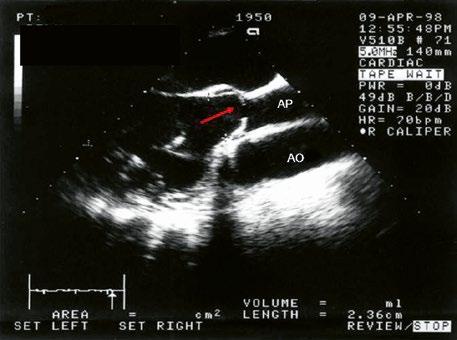

Izovaná PS je nejčastěji valvární, v dětství bývá stenotická chlopeň jemná, poddajná, se srůstem komisur a centrálním otvorem, cípy se v systole vydouvají (doming) (Obr. 45.36, Obr. 45.37). Asi v 15 % je chlopeň myxomatózně ztluštělá, dysplastická, rigidní, s málo pohyblivými cípy (typické pro syndrom Noonanové). V dospělosti dochází k degenerativním změnám a kalcifikaci abnormální pulmonální chlopně (Obr. 45.38).

Obr. 45.36 Valvární pulmonální stenóza, doming cípů, jemné cípy, srůst komisur (TEE, longitudinální projekce) AP – kmen plicnice, PK – pravá komora, PS – pravá síň

Obr. 45.37 Valvární stenóza plicnice, jemná chlopeň, doming cípů, TEE, longitudinální projekce, pacient s transpozičním postavením velkých tepen, aorta (AO) je vepředu, plicnice (AP) vzadu